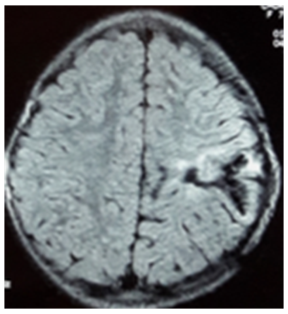

Based in this typical finding, the diagnosis of hydatid cyst of the brain was made. The thorax and abdomen were also observed with CT scans. No lesion was seen on careful examination of the liver, lungs, and other organs. Serological tests for hydatid diseases were positive. The patient was operated and the cyst was removed unruptured. The pseudocyst capsule was then completely removed. Surgery and histology confirmed the hydatid disease. MR six months later demonstrates no recurrence of the cyst (Figure 2).

Figure 2: Cerebral MRI: FLAIR axial image showing no recurrence of the cyst.